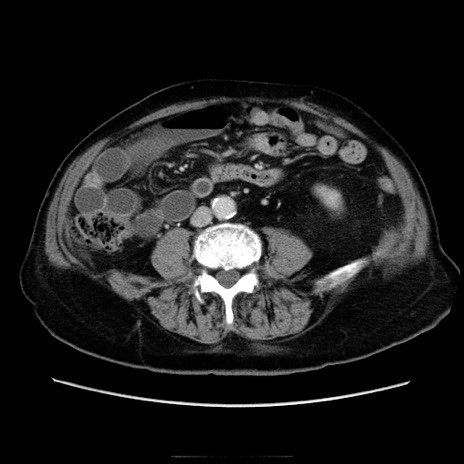

症例21(横断像)

【症例】70歳代男性

【主訴】腹痛

【現病歴】肝硬変・肝細胞癌にてかかりつけの方。約9時間前に食後より腹痛出現。症状が徐々に増悪し、嘔吐出現したため来院。

【既往歴】肝硬変、肝細胞癌(RFA、TACE後)

【身体所見】意識清明、表情苦悶様、BT 36℃、BP 129/78mmHg、P 88bpm、SpO2 97%(RA)、右上腹部から心窩部にかけて圧痛あり、反跳痛なし、筋性防御あり。

【データ】WBC 5800、CRP 0.16